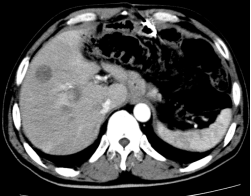

患者林##,男性,48岁,以2008.07.10于我院行“根治性全胃切除术”,病理分期:PT4N3M0,术后一个月复查CT:肝内多发占位,考虑转移癌。先后予化疗、肝动脉灌注化疗及栓塞、肝脏转移瘤射频消融、粒子植入及再次手术等综合治疗;2014.07.22复查胸部CT示右肺下叶和左肺上叶转移,化疗和肺结节粒子植入等综合治疗。现已无瘤存活8年,2016.6.19门诊随访,一般情况良好,生活质量高。

3个月前复查CT图片